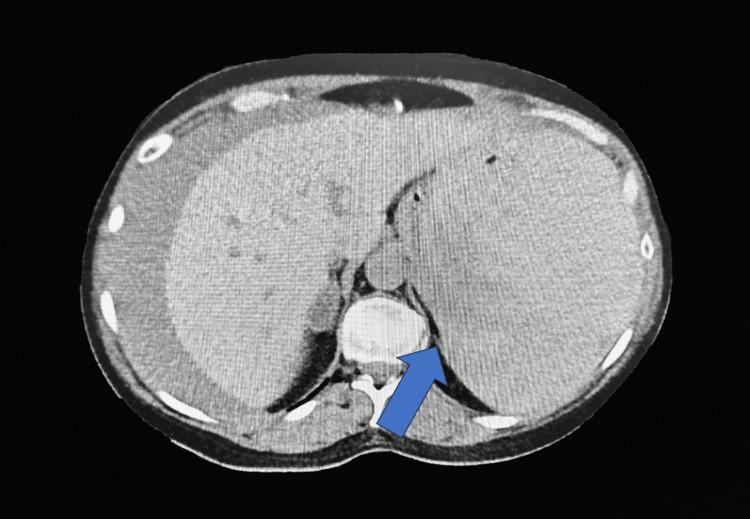

Splenic rupture of all causes is a potentially life-threatening event for patients. The infrequency of atraumatic splenic rupture (ASR) poses a significant diagnostic challenge due to atypical findings. ASR is commonly due to a spleen with an underlying disease process such as malignancy, infection, coagulopathies, or neoplasms. However, ASR without an identifiable cause is rare and poses further complexity. In this case, a 57-year-old woman with a history of hypertension presented to the emergency department complaining of chest pain and was found to have a splenic hematoma. She underwent splenic artery embolization due to her continued hemodynamic instability. The patient was ultimately treated with a splenectomy, as embolization was unsuccessful. Gross pathology revealed no underlying disease processes, nodules, or masses. Splenic hemorrhage due to atraumatic rupture of the spleen is rare and without known pathology. The case illustrates the need for providers to have high clinical suspicion of such a diagnosis to stabilize and surgically manage these patients. Few instances of ASR without an identifiable cause are found in medical literature, and further knowledge of the subject is needed.

各种原因导致的脾破裂对患者来说都是潜在的危及生命的事件。非创伤性脾破裂(ASR)发生率低,因其表现不典型,给诊断带来了重大挑战。ASR通常是由于脾脏存在潜在疾病过程,如恶性肿瘤、感染、凝血功能障碍或肿瘤。然而,无明确病因的ASR很少见,且会带来更多复杂性。在本病例中,一名有高血压病史的57岁女性因胸痛就诊于急诊科,被发现有脾血肿。由于她持续存在血流动力学不稳定,接受了脾动脉栓塞术。最终患者接受了脾切除术,因为栓塞术未成功。大体病理检查未发现潜在疾病过程、结节或肿块。无创伤性脾破裂导致的脾出血很少见,且无已知病理情况。该病例表明,医疗人员需要对此类诊断保持高度临床怀疑,以便稳定病情并对这些患者进行手术治疗。医学文献中很少有无明确病因的ASR病例,对此主题还需要进一步了解。